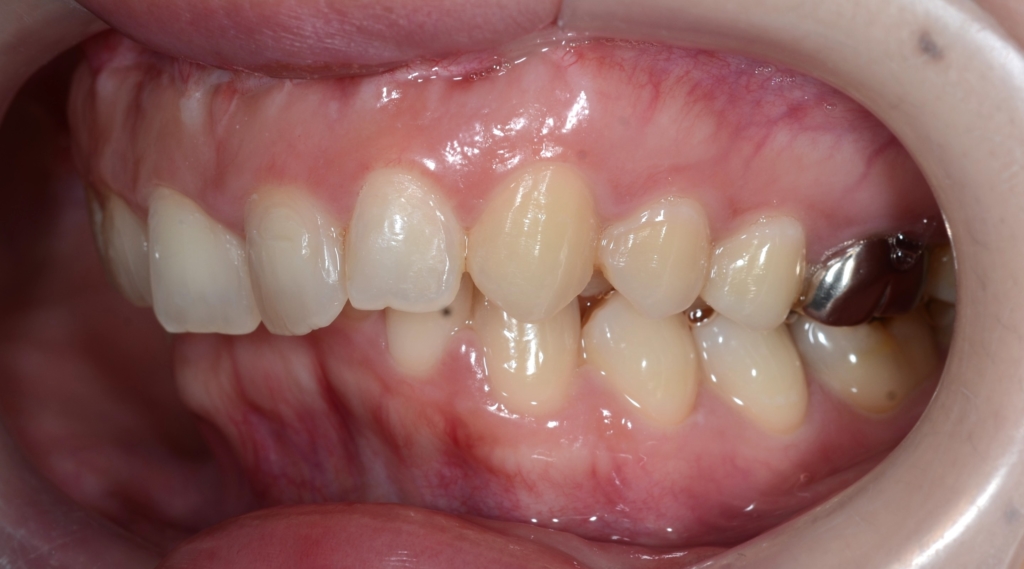

【Before】

【治療方針】

1.アンカースクリューを用いて、上顎前歯を圧下させてガミースマイルの改善を図る

2.その後、抜歯をしてスペースを確保して、上の前歯を最大限に引っ込める

という治療計画にて、矯正を進めることにしました。

【抜歯】

上の左右の奥歯を1本ずつ計2本抜歯(前から4番目の第一小臼歯です)

下は非抜歯です